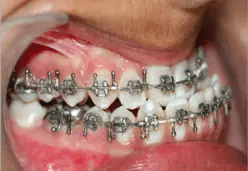

A PATIENT NAMED KOMAL , 21 YEARS FEMALE REPORTED TO THE OUTPATIENT DEPARTMENT OF ORAL AND MAXILLOFACIAL SURGERY OF FACULTY OF DENTAL SCIENCES, SGT UNIVERSITY GURGAON WITH A CHIEF COMPLAINT OF EXCESSIVELY PROMINENT CHIN AND PROTRUDED LOWER LIP SINCE LAST 6 YEARS. EXTRAORAL EXAMINATION REVEALED MESOCEPHALIC HEAD AND MESOPROSOPIC FACIAL FORM WITH A CONCAVE FACIAL PROFILE. THE PATIENT PRESENTED WITH A GROSS FACIAL ASYMMETRY WITH SUNKEN CHEEKS, REDUCED MALAR PROMINENCE, A DEEP MENTOLABIAL SULCUS AND AN ANTERIORLY DIVERGENT FACE. LIPS WERE COMPETENT. ON INTRAORAL EXAMINATION, A CLASS III MOLAR RELATION WAS SEEN WITH AN INTERINCISAL OPENING OF 42 MM AND MIDLINE SHIFTED TO THE LEFT SIDE. A HYPOPLASTIC UPPER LIP WITH DEVIATION OF JAW TO LEFT SIDE WHILE CLOSURE OF THE MOUTH WAS SEEN.

CEPHALOMETRIC ANALYSIS WAS DONE FOR THE PATIENT WHICH CONFIRMED THE CLINICAL FINDINGS. THE TREATMENT WAS PLANNED UNDER THREE DISTINCT PHASES.

PRESURGICAL ORTHODONTICS

ORTHOGNATHIC SURGERY

POSTSURGICAL ORTHODONTICS

MAXILLARY ADVANCEMENT WITH DOWNGRAFTING ALONG WITH BILATERAL SAGGITAL SPLIT OSTEOTOMY WAS DONE UNDER GENERAL ANESTHESIA. MAXILLARY ADVANCEMENT WAS DONE BY 6 MM ALONG WITH 6 MM OF MANDIBULAR SETBACK WAS DONE. BOTH MAXILLA AND MANDIBLE WERE FIXED INTO THE DESIRED POSTION USING 2 MM CHAMPY’S MINIPLATE. PRIMARY CLOSURE WAS DONE USING 3-0 VICRYL SUTURES.